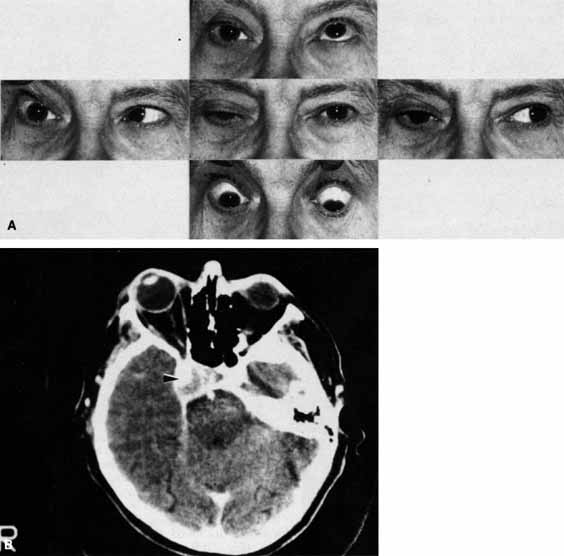

Pupillary dilation and reduction of accommodation occur when parasympathetic innervation to the globe is damaged. When the damage occurs at or distal to the ciliary ganglion, Adie's pupil results. The pupil contracts poorly to light but better to accommodation. The pupil movements are slow and poorly coordinated (vermiform). Generally there is a reduction in accommodation range. The pupil in such cases develops a supersensitivity to parasympathomimetics such as 0.1% pilocarpine. Orbital trauma, inflammation, and intraocular laser treatment may result in Adie's pupil. Deep orbital dissection lateral to the optic nerve in the region of the ciliary ganglion or around the anterior optic nerve where the short ciliary nerves run may also produce Adie's pupil. The denervation may only be sectoral, resulting in an abnormally contoured pupil which demonstrates slow tonic contracture only in the involved sector. Because the parasympathetics have diverged from cranial nerve III prior to entering the ciliary ganglion, pupillary dilation which contracts with 0.1% pilocarpine is not usually associated with neurogenic ophthalmoplegia (Fig. 19).

Fig. 19 A. A patient underwent endoscopic exploration of the right ethmoid and maxillary sinus for persistent epistaxis. Postoperatively the patient demonstrates right proptosis, restricted extraocular movements of the right eye, and a dilated right pupil. Instillation of 0.1% pilocarpine resulted in miosis on the right and no change on the left. Computed tomography (CT) shows a vessel clip lateral to the optic nerve (arrow), near the position of the ciliary ganglion. B. Coronal CT scan showing the clip lateral to the optic nerve (arrow).